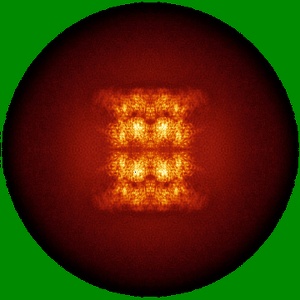

Human p97/VCP structure with a triazole inhibitor (NSC799462/dodecamer)

Single-particle3.33 Å

Sample: p97/VCP AAA+ ATPase/NSC799462

Mechanism of allosteric inhibition of human p97/VCP ATPase and its disease mutant by triazole inhibitors.

(2024) Commun Chem , 7 , 177 - 177